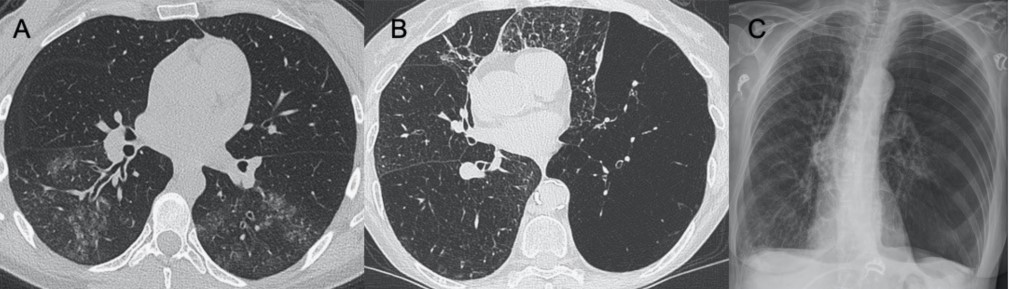

?巨細(xì)胞病毒

● CXR:彌漫性和雙側(cè)實(shí)變伴間質(zhì)受累。

● CT:間質(zhì)和肺泡浸潤,雙側(cè)和不對稱性GGO區(qū)域,與實(shí)質(zhì)實(shí)變區(qū)域相關(guān)。

圖8 巨細(xì)胞病毒性肺炎。圖(A–C)顯示其輕度實(shí)質(zhì)受累的情況。圖(D、E)顯示患者有彌漫性GGO和鋪路石征,胸片(F)中同樣可見。